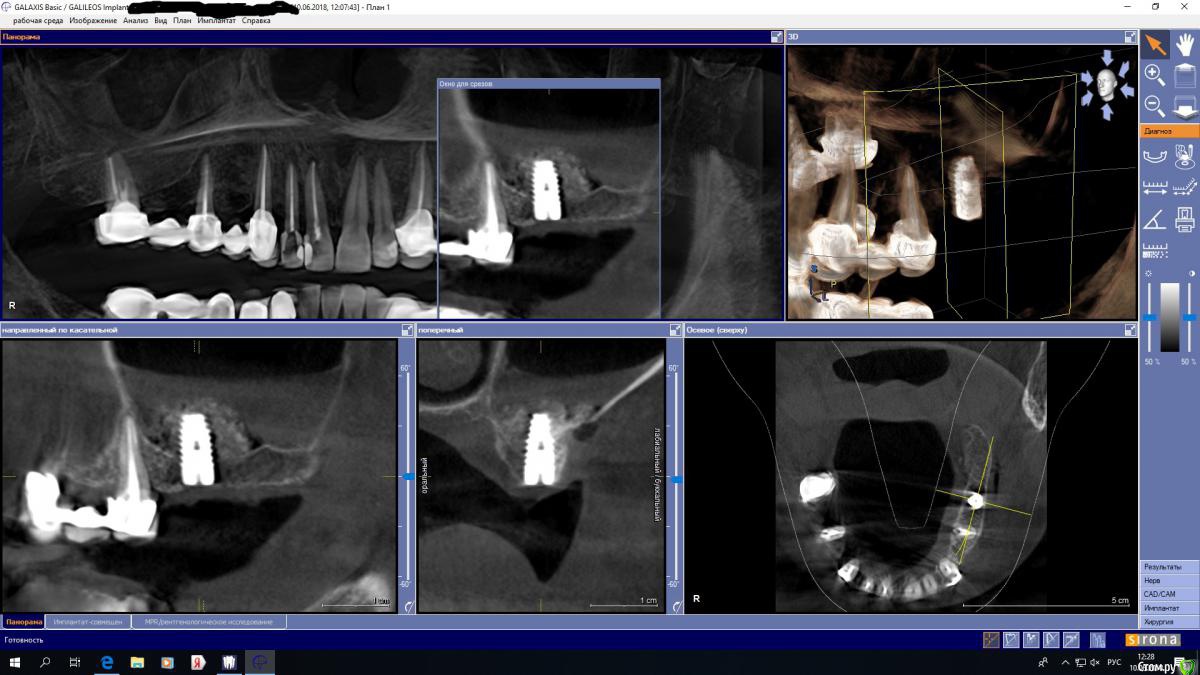

Ponchik Опубликовано 10 июня, 2018 Автор Поделиться Опубликовано 10 июня, 2018 (изменено) Я сделал это! Первый синус! Перфо не увидел, но наверное оно есть, судя по уровню жидкости(кровь,физраствор?). Мембрану внутрь уложил. Второй окно закрыл, но без пинов. Графт таки нашел срочно L. Ну как? много накосячил? Изменено 10 июня, 2018 пользователем Ponchik 2 Ссылка на комментарий

Aquarius Опубликовано 10 июня, 2018 Поделиться Опубликовано 10 июня, 2018 Отлично . Но окно вроде не доутромбовано и опять же можно было и закрытым пойти 1 Ссылка на комментарий

Ponchik Опубликовано 10 июня, 2018 Автор Поделиться Опубликовано 10 июня, 2018 Заметил про неплотность. Можно было давить на графт сильнее. Боялся прорвать или передавить. Первый раз граф использовал. Ранее стучал и поднимал остеотомии. Тут решил что порву наверное. Ссылка на комментарий

dok1 Опубликовано 10 июня, 2018 Поделиться Опубликовано 10 июня, 2018 Чёт слизистая толстовата.. Неспокойная. Ссылка на комментарий

Ponchik Опубликовано 11 июня, 2018 Автор Поделиться Опубликовано 11 июня, 2018 (изменено) Я думал это жидкость. Неделю назад была тоненькая. Не более 0.5мм. Теперь уже не переиграть. Клинически пациентка была здорова. Изменено 11 июня, 2018 пользователем Ponchik Ссылка на комментарий

Nazim_NV86 Опубликовано 11 июня, 2018 Поделиться Опубликовано 11 июня, 2018 Сделайте контроль через 4 месяца и увидите что слизистая 90% нормализуется. Недосыпания нестрашны, но не всегда. Зависит от толщины имеющейся кости. А так всё нормально. Ссылка на комментарий